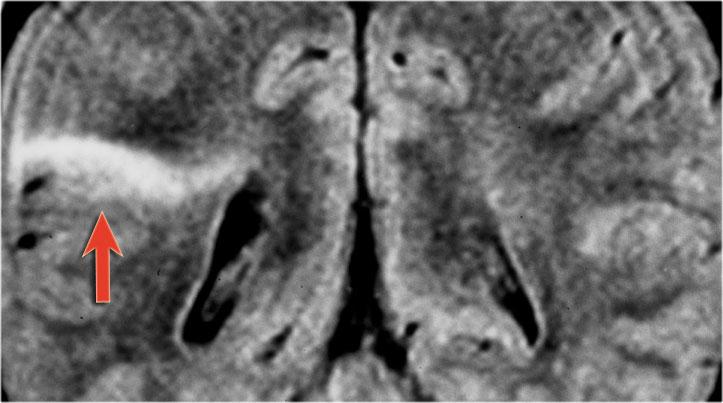

Hình ảnh T2W và FLAIR mặt phẳng coronal cho thấy xơ cứng thùy thái dương trong bên phải.

Lưu ý tình trạng mất thể tích, biểu hiện của teo não, gây giãn thứ phát sừng thái dương của não thất bên.

Tín hiệu cao trong hải mã phản ánh tình trạng gliosis.

Hình ảnh cho thấy xơ cứng thùy thái dương trong với hải mã tăng tín hiệu và teo nhỏ (mũi tên đỏ), kèm theo giãn thứ phát sừng thái dương trái của não thất bên trái.

Cũng cần lưu ý tình trạng tăng tín hiệu dưới vỏ não kết hợp ở thùy thái dương trái, gợi ý loạn sản vỏ não khu trú.